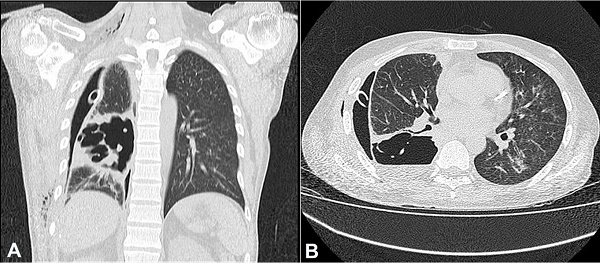

On admission to the Infectious Diseases Department, the patient was pale, disoriented, had tachycardia, decreased breath sounds at the base of the right hemithorax, which had a thoracic drainage tube. A new chest x-ray revealed right pneumothorax and an ovoid, homogeneous opacity without any air-fluid level in the right lower lung lobe, and the presence of thoracic drainage (Figure 2). A non-contrast chest computed tomography was performed, revealing the pneumothorax with irregular cavitation in the right hemithorax.

The cavitation measured 10.0 × 7.5 × 5.0 cm, had thickened walls, and was located in the pleuropulmonary interface of the posterior margin of the right lower lobe. Its interior showed tissue bands indicating permeation and fluid collection consistent with an abscessed/necrotizing lung lesion in contact with the pleural space. Centrilobular ground-glass opacities, predominantly in the central regions of the left lung, were also visualized, probably representing a non-specific, inflammatory/infectious process (Figures 33B).